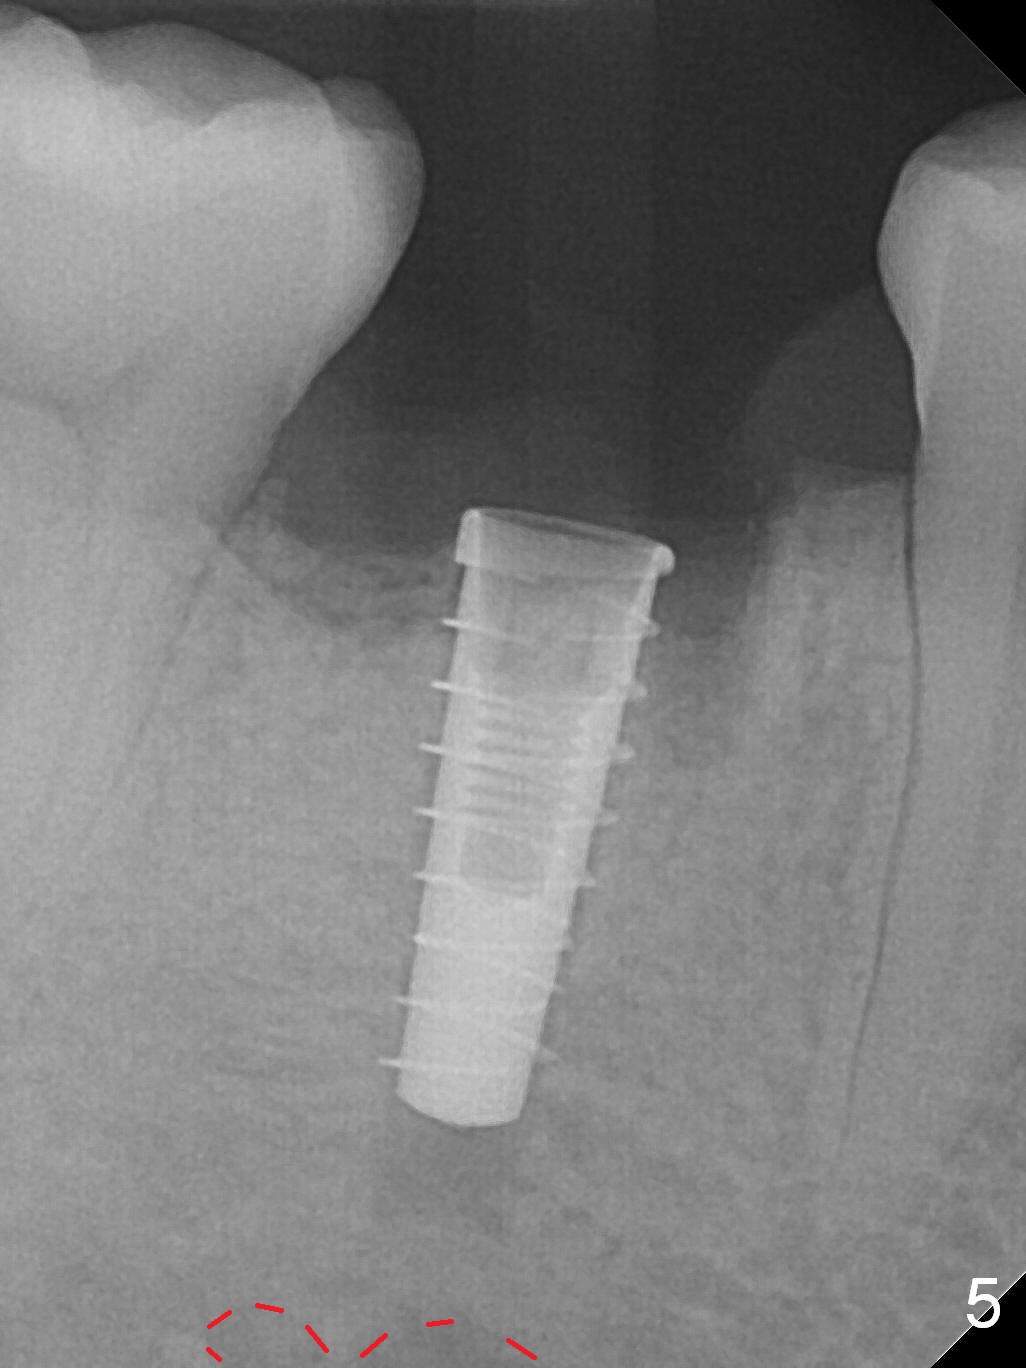

The lower 2nd primary molar has buccal furca lesion (Fig.1 *) with the thin buccal plate (Fig.2). Osteotomy is initiated in the sloped septum (Fig.3). After use of Magic Drill (MD) 3.3 mm for 13 mm and MD 3.8 mm for 11 mm, placement of a 4x11 mm IBS implant meets resistance because of the dense bone (Fig.4-6, red dashed line: Mental Loop) with final insertion torque >50 Ncm. After placement of a 6x4(3) mm abutment and autogenous bone in the remaining shallow sockets (Fig.6), a provisional is fabricated (Fig.7). Finally periodontal dressing is applied. Impression is taken 3 months postop (Fig.8). Buccal infection develops 2 weeks post cementation (Fig.9). When the crown/abutment is removed, there is no residual cement. The implant threads can be felt through the fistula. After soft tissue debridement and copious irrigation, Arestin is placed in the fistula. The latter disappears 15 days post debridement. The patient feels better and moves out of state. It appears that early periimplantitis develops because of the preexisting buccal furca lesion and failure to place the implant deep. The implant will be placed deep after loosening a little (since there is apical space (Fig.8 white line)) or removed, truncated at the apex and placed lower than the buccal crest.